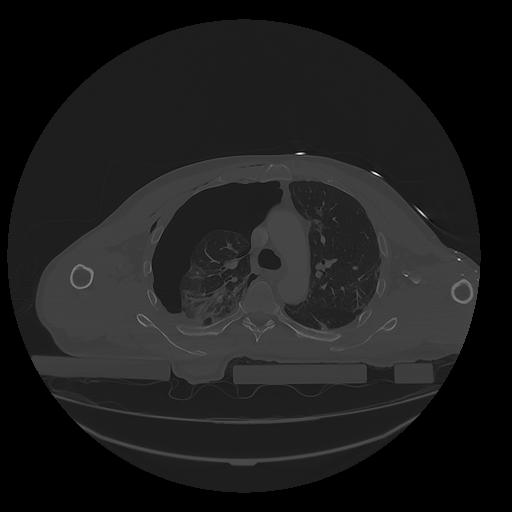

31 PULMON,CE,Vol,1.0,PULMON,,